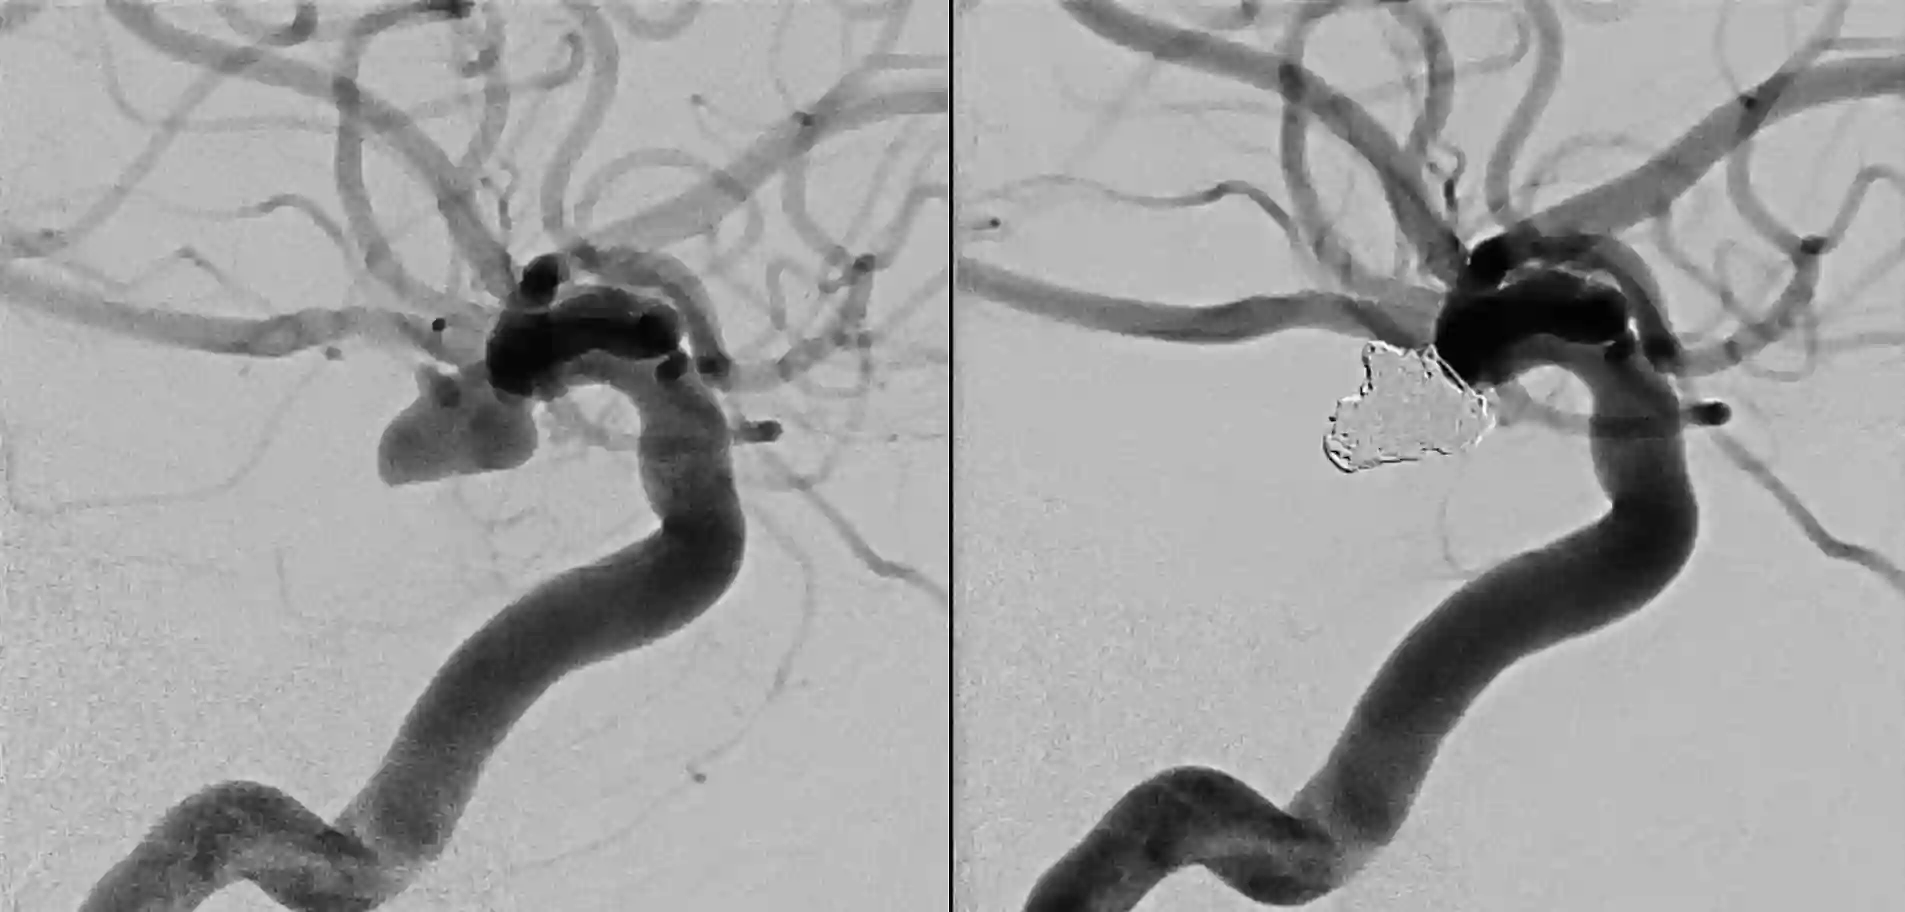

Ein Aneurysma der Arteria communicans posterior vor (links) und nach (rechts) coiling.